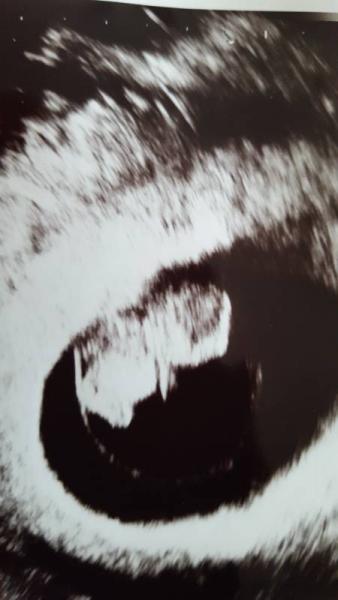

Danke für eure lieben Worte Es war tatsächlich alles prima beim Termin, ich bin sooo erleichtert! Mein Krümelchen ist 2 cm groß und das Herz blubbert fleißig. Ärmchen und Beinchen hat man auch schon gesehen. Nur bewegen wollte er sich nicht, die Ärztin hat auf meinem Bauch rumgedrückt, damit er aufwacht und zappelt, aber er hat selig weiter geschlafen. Ganz die Mami. Jetzt werde ich versuchen mir nicht mehr solche Sorgen zu machen. Ich wünsche allen, die auch diese Woche noch Termin haben alles gute!!

Bild zu